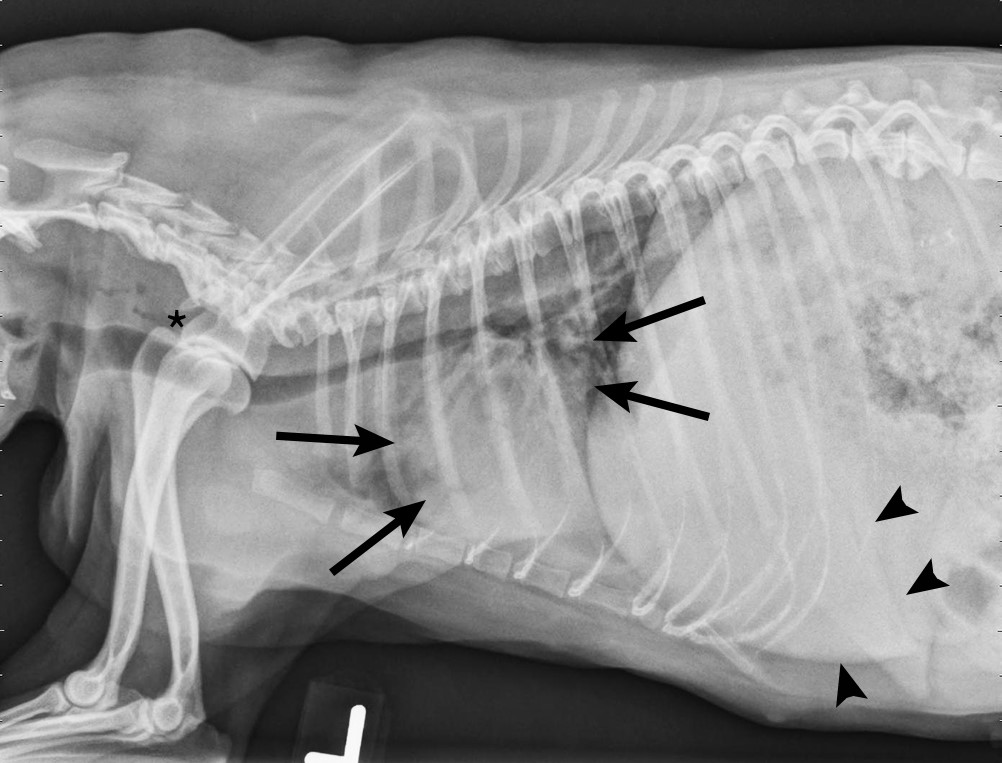

Canine infectious respiratory disease complex (cirdc) refers to a syndrome of diseases that can be caused by several different bacterial and viral pathogens.

Canine infectious respiratory disease complex what is it, and what can be done?